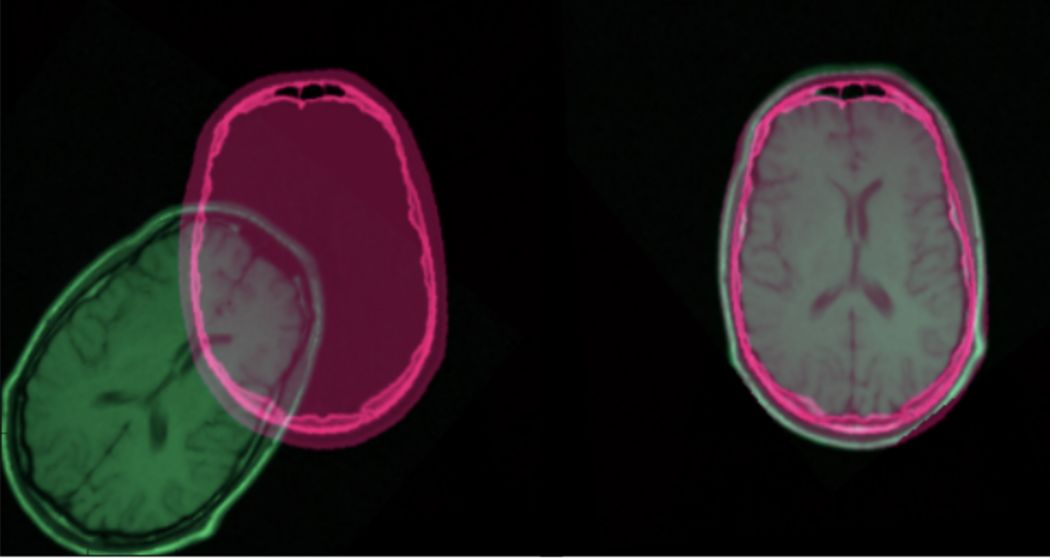

图像配准具有广泛的应用,适用于同一个场景中有多张图像需要进行匹配或叠加。在医学图像领域以及卫星图像分析和光流(optical flow)方面非常普遍。

CT扫描和MRI配准